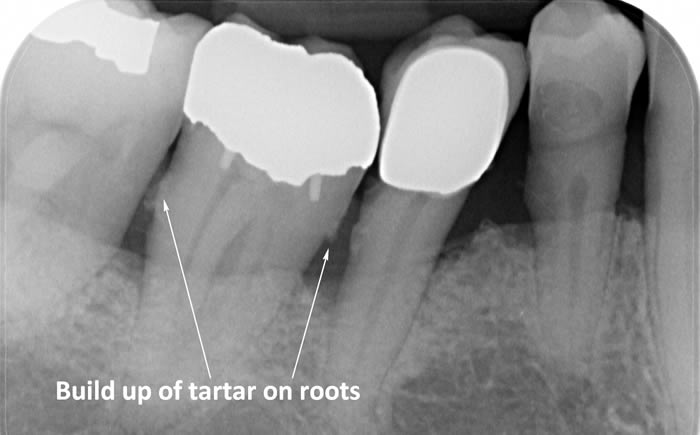

The diagrams below show the different stages of gum disease

In addition to helping patients improve their oral hygiene our Hygienist’s will also carry out thorough scaling and polishing to remove any build-up of calculus (tartar) which has formed on the teeth above the gum level.

Calculus (tartar) is the hard deposit which forms on the teeth in areas where plaque is left undisturbed. Calculus is too hard to brush off with a toothbrush and needs to be removed by the Dental Hygienist with special scaling instruments.

In cases of advanced gum disease our Hygienist’s will also carry out deep scaling which cleans the root surfaces beneath the gum level. When pockets develop in the gums around the teeth plaque bacteria and calculus form on the root surfaces of the teeth and are protected from toothbrushing by the overlying gum. However, our Hygienist’s have special thin scaling instruments which can go down inside the pockets to clean the root surfaces. This treatment is carried out in small sections under local anaesthetic to ensure that you are comfortable throughout the treatment.